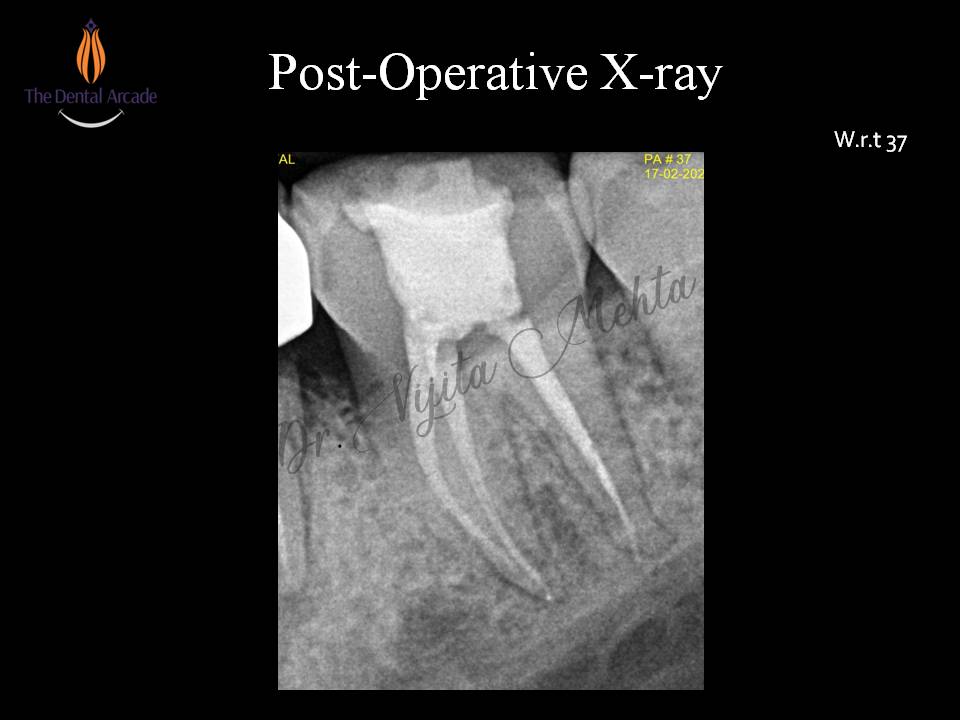

Root canal Treatment

Root canal treatment-Part II

Root canal treatment-Part I